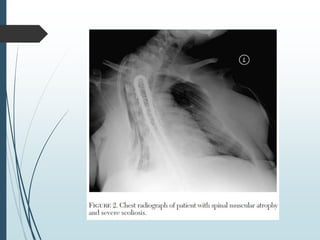

 a atrofia espinhal precisou de IOT e TQT por retenção de

secreção 10h após o parto (escoliose intensa).